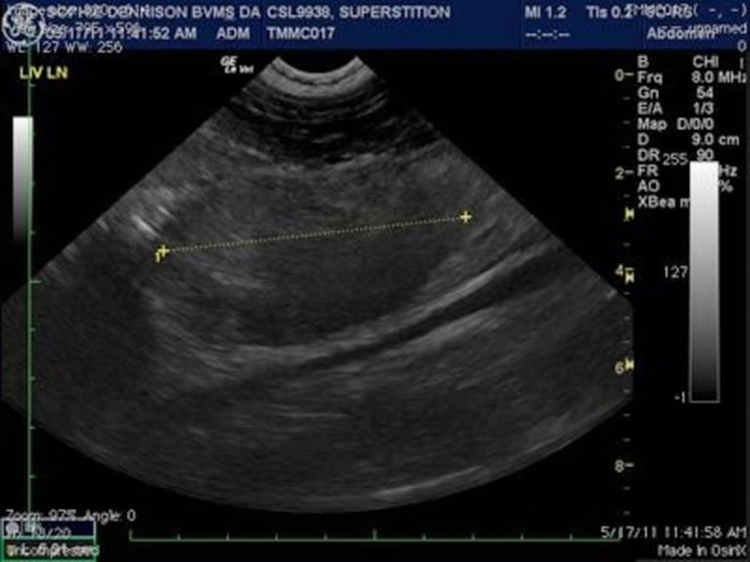

海洋哺乳动物中心为一只加州海狮照超音波,测量腹部肿瘤。这只昵称为“迷信”的海狮死于癌症。 PHOTOGRAPH BY THE MARINE MAMMAL CENTER